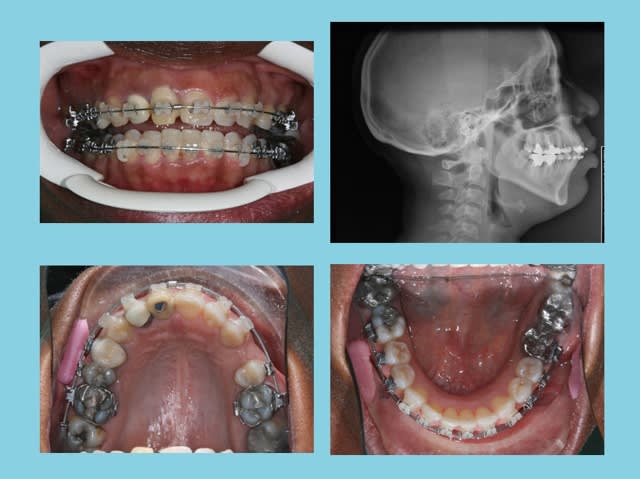

SUITE

En cours ixr16w - Eugenol

Augmentation de longueur d’arcade = 15 mm.